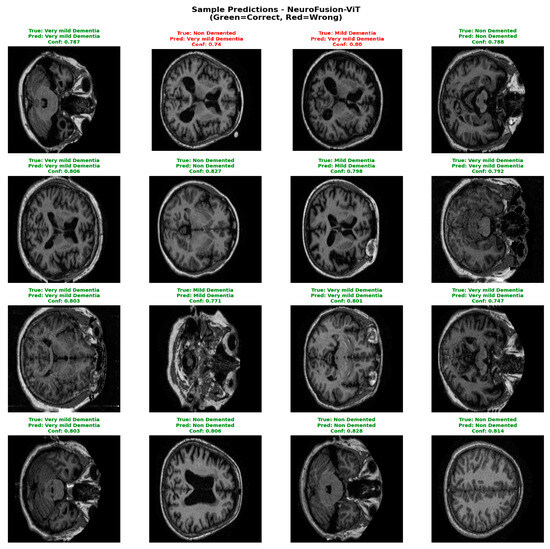

NeuroFusion-ViT: A Hybrid CNN–EVA Transformer Model with Cross-Attention Fusion for MRI-Based Alzheimer’s Stage Classification

by Derya Öztürk Söylemez and Sevinç Ay Doğru

Diagnostics 2026, 16(5), 754; https://doi.org/10.3390/diagnostics16050754 - 3 Mar 2026

Background: Alzheimer’s disease is the most common type of dementia and a progressive neurodegenerative disease that begins with neuronal damage and leads to a reduction in brain tissue. Currently, there is no cure for this disease, and existing approaches focus on alleviating symptoms. Methods: This study proposes NeuroFusion-ViT, a highly accurate and computationally efficient hybrid deep learning model for early-stage detection of Alzheimer’s disease. The model combines an EVA-02-based Vision Transformer (ViT) with the ConvNeXt-Small CNN architecture, providing powerful representation learning that can process both global context and local details. The proposed Gated Cross-Attention Fusion (G-CAF) mechanism dynamically combines two different features, offering high discriminative power and model stability. Results: In experiments conducted on the OASIS MRI dataset, the model achieved 99.86% accuracy, 0.9989 Macro F1, and 0.999 ROC-AUC values, demonstrating clear superiority over single-modal and hybrid models described in the literature. Furthermore, 5-fold cross-validation results also support the model’s high generalizability. Ablation studies showed that each of the components—cross-attention, gate mechanism, Dual LayerNorm, and FFN-Dropout—made a meaningful contribution to performance. Conclusions: The results demonstrate that the NeuroFusion-ViT architecture offers a reliable, stable, and clinically applicable solution for Alzheimer’s stage classification. Full article